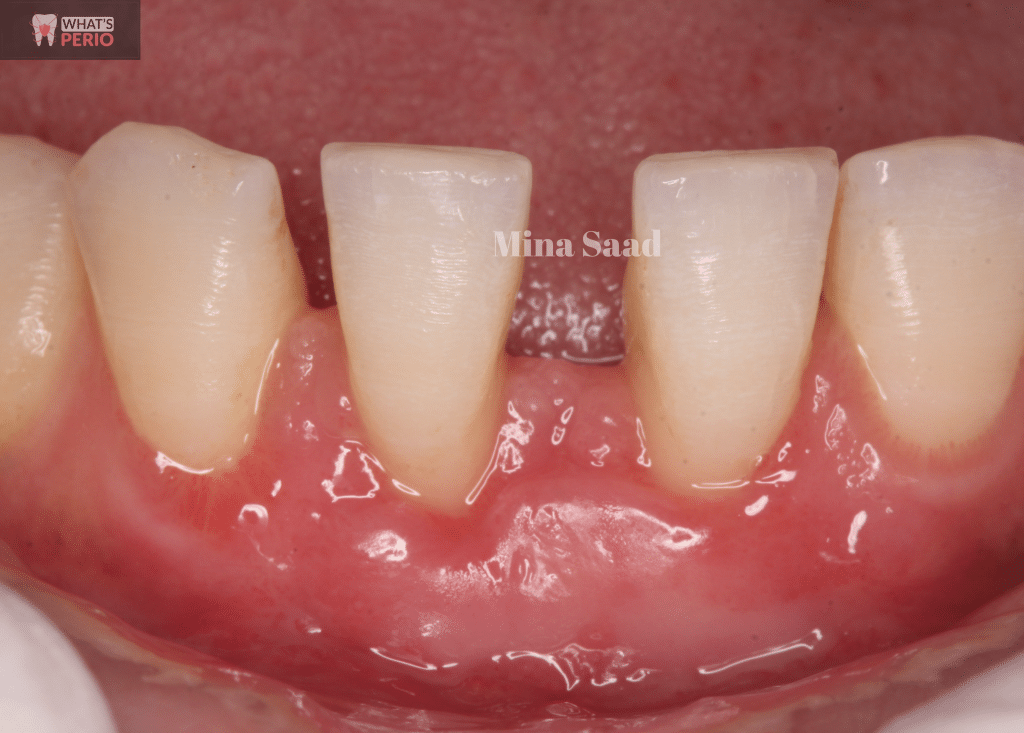

Preoperative photo

Microvasculature is very apparent in alveolar mucosa

Recession depth (RD) for right central = 3 mm.

"RD is the distance between cemento-enamel junction (CEJ) & free gingival margin"

Recession depth (RD) for left central = 2 mm.

Preoperative chart measurements "Buccal"

Width of kerstinized gingiva (WKG).... The distance between free gingival margin & Muco-gingival junction (MGJ)

1-Marginal gingival recession was noted in lower 2 central incisors.

2-Interdental papillary loss between the 2 central incisors especially in the mesial aspects due to interdental attachment loss.

3-Spacing between central incisors & lateral incisors but it was more between the 2 central incisors.

4-Slight rotation of the 2 central incisors.

5-Very thin gingival phenotype or biotype (tissue thickness) which is one of the risk factors for gingival recession. “Note that the microvasculature was apparent in the whole alveolar mucosa”.

6-Very narrow zone of keratinized tissue especially all around the 2 central incisors. “almost 1mm from the free gingival margin to the mucogingival junction”.

7-Ginigva is inflamed due to presence of local irritants “calculus deposits” adherent on the proximal surfaces of both central incisors.